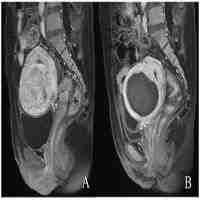

| Abstract | A novel multifunctional nanotheranostic agent with targeting, redox-responsive ultrasound imaging and ultrasound imaging-guided high-intensity focused ultrasound (HIFU) therapy (MSNC-PEG-HA(SS)-PFH, abbreviated as MPH(SS)-PFH) capabilities is developed. The redox-responsive guest molecule release and ultrasound imaging functions can be both integrated in such a 'smart' theranostic agent, which is accomplished by the redox-triggered transition from the crosslinking state to retrocrosslinking state of the grafted polyethylene glycol-disulfide hyaluronic acid molecules on the particle surface when reaching a reducing environment in vitro. More importantly, under the tailored ultrasound imaging guiding, in vivo Hela tumor-bearing nude mice can be thoroughly and spatial-accurately ablated during HIFU therapy, due to the targeted accumulation, responsive ultrasound imaging guidance and the synergistic ablation functions of nanotheranostic agent MPH(SS)-PFH in the tumors. This novel multifunctional nano-platform can serve as a promising candidate for further studies on oncology therapy, due to its high stability, responsive and indicative ultrasound imaging of tumors, and enhanced HIFU therapeutic efficiency and spatial accuracy under ultrasound-guidance. |